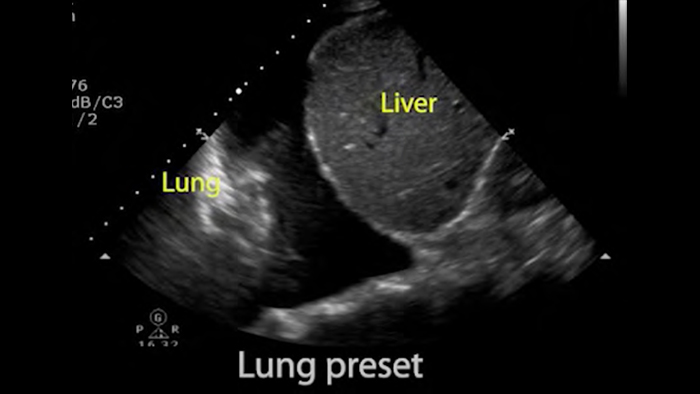

Utilice Lumify para la evaluación de las vías respiratorias y pulmonares

Las soluciones Lumify POCUS pueden ayudarle a detectar el tubo endotraqueal dentro de la tráquea, ayudar en los procedimientos de cricotirotomía emergentes, en el diagnóstico de derrame pleural y enfermedades alveolares intersticiales.

Conceptos básicos del ultrasonido pulmonar